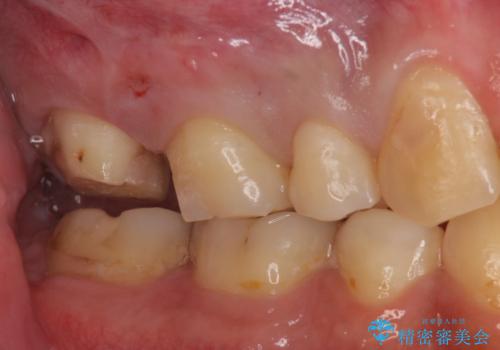

- 一番奥の銀の詰め物を白くしたいとのことで来院。

セラミックの詰め物のやりかえだと範囲が多く、割れてしまうリスクがあります。

そのため、割れるリスクが少ない詰め物ではなく、被せ物による治療(ジルコニアクラウン)を行いました。

また、隣の歯も白い樹脂の下が虫歯になっており、セラミックの詰め物(e-maxインレー)による修復をしました。